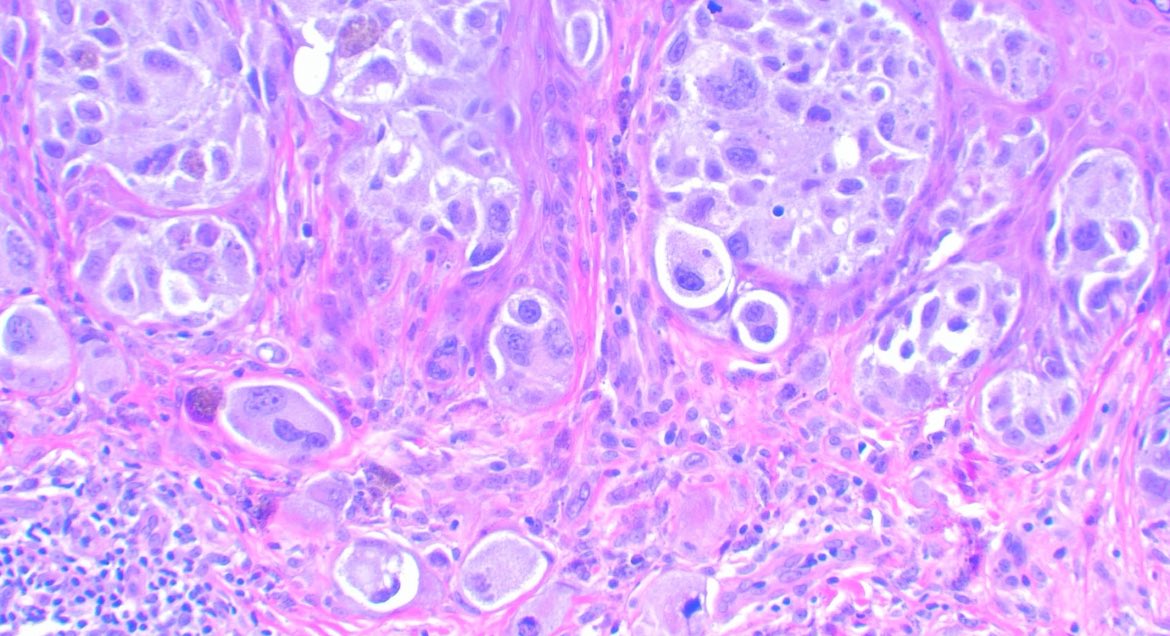

75-year-old male with a 4 cm mass in the lower pole of the right kidney. CA9 diffusely positive = CCRCC with a cute morphological appearance. #gupath GU Pathology Society (GUPS) International Society of Urological Pathology